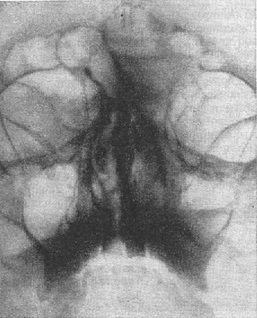

![]() Рис. 14. Невринома правого слухового нерва. Рентгенограма пірамід скроневих кісток по Стенверсу. Праворуч визначається різке розширення внутрішнього слухового проходу. Рис. 15 (праворуч). Гострий синуит. Рентгенограма придаткових пазух носа. Вертикальне положення голови хворого і касети. Видно горизонтальні рівні рідини в правій лобовій і правої гайморової пазусі. |

Повітряні простору повітроносних кісток при запальних захворюваннях виконані патологічним вмістом (серозний або гнійний випіт, набрякла слизова оболонка, поліпи, кісти, грануляції) або відбувається порушення цілості їх стінок в результаті перелому або деструкції при ураженнях пухлиною. У пазухах, переважно в лобних, іноді вперше вдається виявити рентгенологічно доброякісну пухлину - остеому. У всіх випадках заміна повітря більш важким вмістом дає рентгенологічний симптом затемнення, інтенсивність якого залежить від його кількості, атомної ваги і об'єму самої пазухи. Рентгенографія при вертикальному положенні голови хворого і касети виявляє рентгенологічний симптом горизонтального рівня рідини в ній (рис. 15). У сумнівних випадках користуються введенням в пазуху йодолипола або майодила.